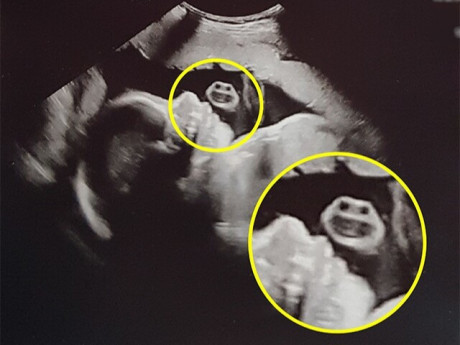

Ở thời điểm này, siêu âm giúp tính tuổi thai cực kỳ chính xác. Ngoài ra, đây cũng là thời điểm duy nhất có thể đo khoảng sáng sau gáy nhằm dự đoán một số bất thường nhiễm sắc thể nguy hiểm (gây bệnh down, dị dạng tim, chi, thoát vị cơ hoành...). Ngoài 14 tuần, việc đo này sẽ không còn chính xác nữa. Nếu khoảng sáng sau gáy tăng, vào tuần thứ 18, thai phụ cần được chọc ối để chẩn đoán bệnh down và siêu âm hình thái xem có dị dạng hay không.

Siêu âm 12-14 tuần là thời điểm duy nhất có thể đo khoảng sáng sau gáy nhằm dự đoán một số bất thường nhiễm sắc thể nguy hiểm. (ảnh minh họa)